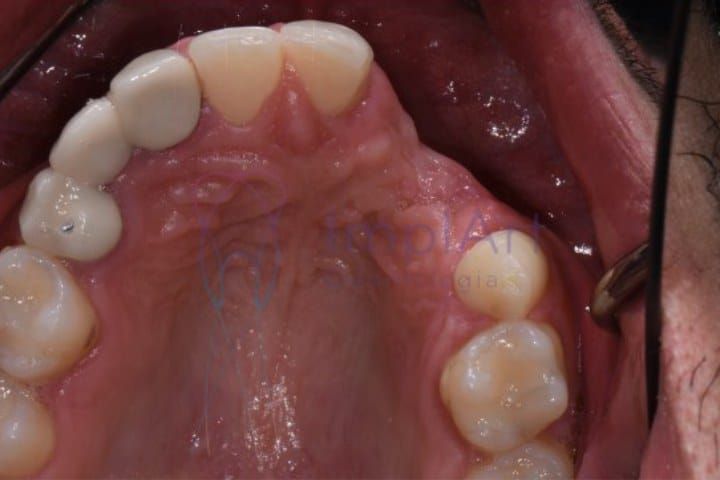

A perda óssea dentária é conhecida como reabsorção óssea dentária. Isso acontece quando o tecido ósseo que sustenta os dentes começa a se desgastar. A condição pode ser irreversível e levar a problemas sérios, como perda de dentes e infecções. Além disso, dificulta tratamentos que usam implantes dentários.

É essencial conhecer os sinais iniciais da reabsorção óssea. Isso obviamente ajuda no diagnóstico, e também no tratamento e para impedir que a doença se agrave. Entre os sinais para você ficar alerta podemos citar dentes com mobilidade, mudanças na mordida e gengivas retraídas, deixando as raízes à mostra.

O diagnóstico costuma ser feito clinicamente, com auxilio de imagens de raio-x. Elas mostram o quão grave é a perda de osso. Se você acha que está com perda óssea dentária, deve comparecer a uma consulta com nossos especialistas, porque um tratamento precoce pode literalmente salvar seus dentes.